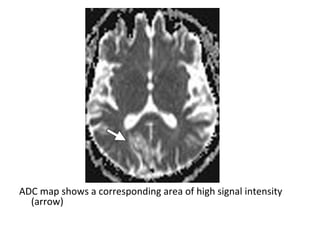

ADC map shows an area of low signal intensity in the right parietooccipital

junction (arrow) , a finding that usually persists for about 1 week , this

area demonstrates high signal intensity at diffusion-weighted imaging (not

shown)